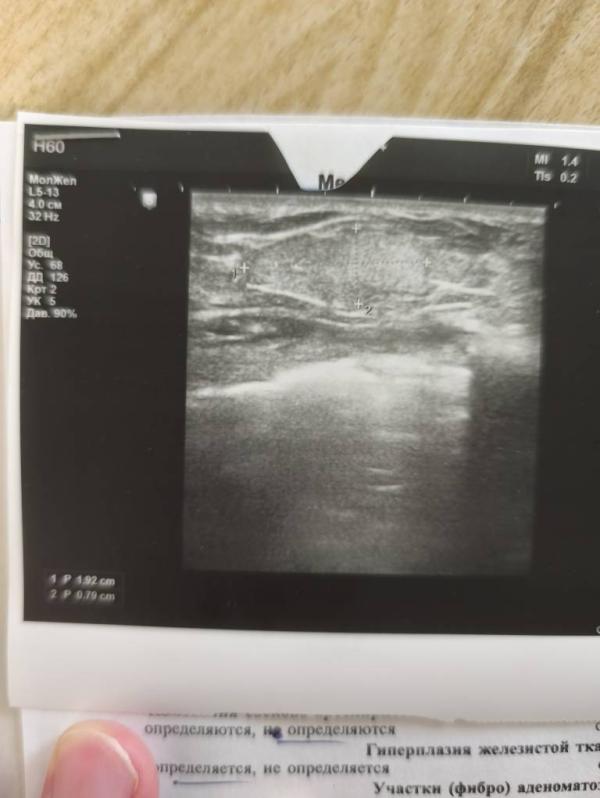

На УЗИ нашли образование 1,8 см на 0,9 см. Но что это, пока не ясно. По цвету, структуре, на опухоль или кисту, или фиброаденому не похоже. Потому что структура у неё внутри, как у всей остальной железы, но она имеет контур и отчётливо определяется руками. Поэтому, возможно, что это просто увеличенная доля железы. Но так как в лактирующей груди опухоль и фиброаденома могут выглядеть иначе, то нужно наблюдать.